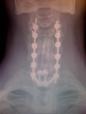

Here is my neck, which was done in 2007.

That’s three inches of bone from my left leg in the center of the sixteen screws. There is hip bone (two inches) in there as well. I was on the table for fourteen hours. I spent five years sleeping in a chair and a year begging for death. I could not talk for over a year because they split my vocal cords. But, I am alive, married for 35 years, and doing great!